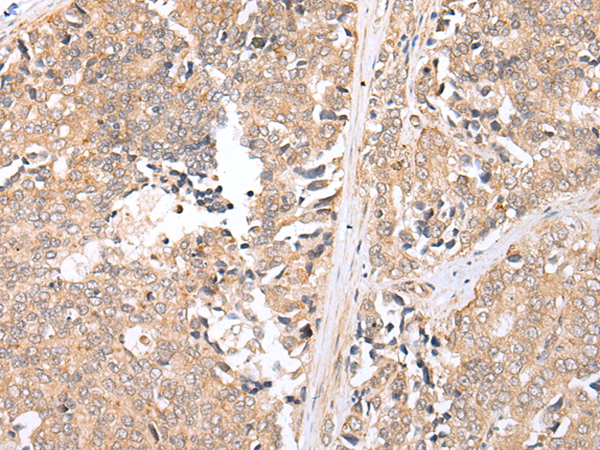

分类: 科研抗体货号: P01920别名: HAT应用: WB,IHC反应种属: Human, Rat